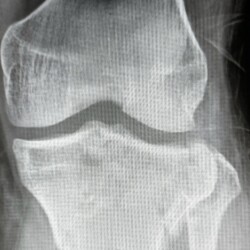

Fratura da patela com importante desvio e fratura cominutiva do 1/3 proximal da tíbia comprometendo a eminência intercondiliana.